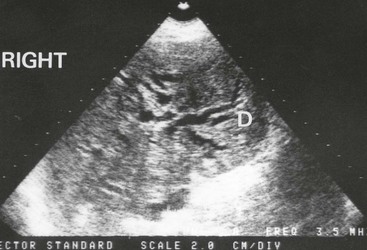

Fig. 18.11 Ultrasonogram showing dilated intrahepatic ducts

An ultrasound scan in an 80-year-old man with obstructive jaundice. This transverse section through the liver shows the characteristic ‘double-barrel shotgun sign’ D, with two parallel tubular structures representing major branches of the bile duct and portal vein. Normally, the portal vein is four times wider than the corresponding bile duct. Here they are the same diameter